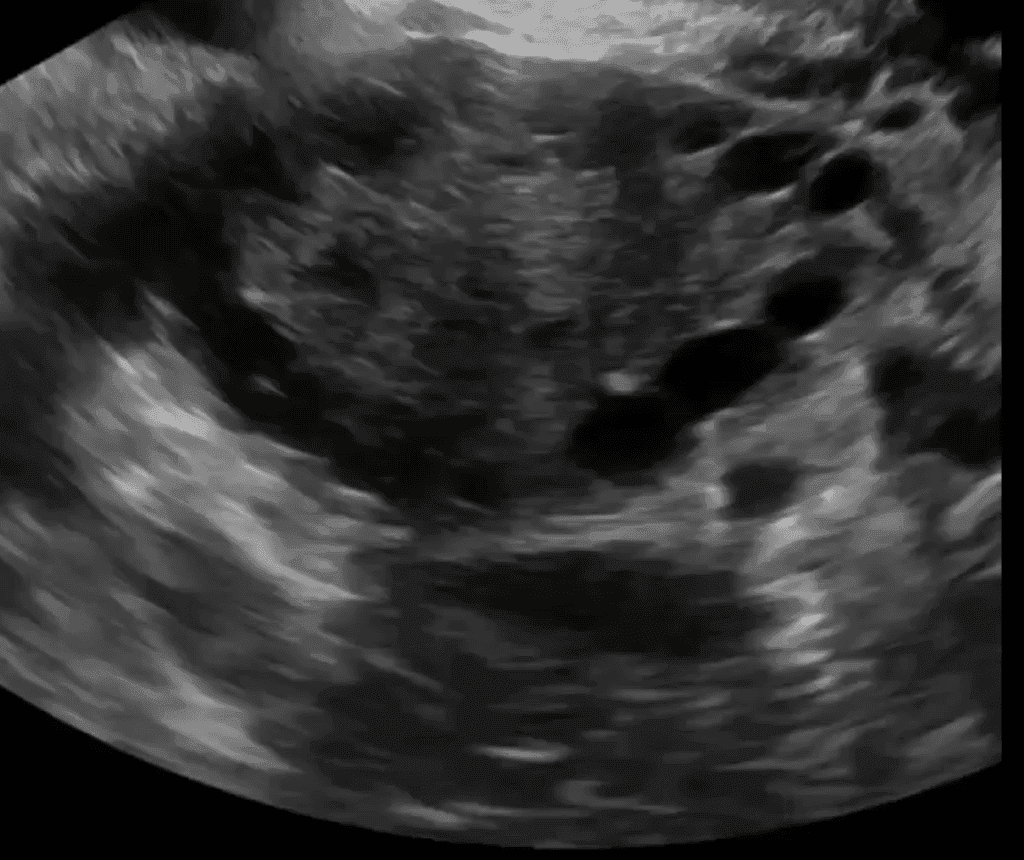

This CME activity provides an in-depth overview of Polycystic Ovarian Syndrome (PCOS), focusing on its diagnostic criteria, clinical manifestations, and role of transvaginal sonography in identifying polycystic ovary morphology (PCOM). Learn about ultrasound features, hormonal imbalances, and treatment options like Metformin and birth control pills.

Understand the sonographic characteristics of PCOS